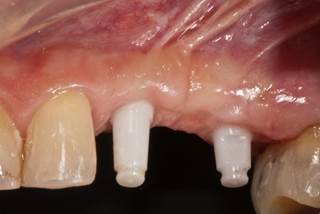

- Pacientes que buscan un resultado especialmente estético en la región anterior

- La encía alrededor de las restauraciones sobre estos implantes siempre tiene un aspecto absolutamente saludable sin signos de inflamación